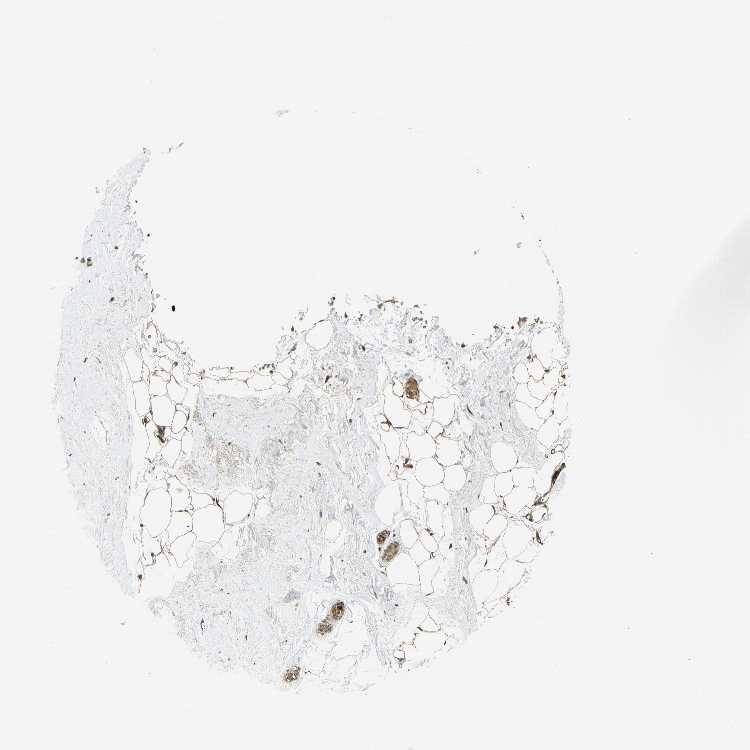

BREAST - Antibody stainingi

Antibody staining in the annotated cell types in the current human tissue is reported as not detected, low, medium, or high, based on conventional immunohistochemistry profiling in selected tissues. This score is based on the combination of the staining intensity and fraction of stained cells.

Each image is clickable and will lead to virtual microscopy that enables deeper exploration of all samples and also displays staining intensity scores, fraction scores and subcellular localization as well as patient and tissue information for each sample.

Antibody CAB012473

Adipocytes Medium

Glandular cells Low

Myoepithelial cells Low